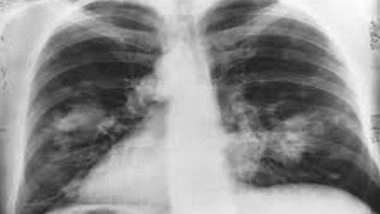

The technology will enable biopsies of endobronchial tumors (tumors inside the windpipe) and will be crucial in improving clinical outcomes for lung cancer patients.

"The minimally invasive procedure is used to remove larger cancerous outgrowths in the lung using a freezing process that prevents bleeding which occurs with a normal biopsy," he said.

He further said that this is one of the safest procedures for tumor debulking. Other equally important roles of Cryo involve diagnosis of ILD (Interstitial lung disease), Sarcoidosis (an inflammatory disease that affects one or more organs), Lymphoma (cancer that begins in infection-fighting cells of the immune system), removal of foreign body and blood clots from lung, recanalization of an obstructive tracheal and/or bronchial tumor, and diagnosis and treatment of Carcinoid tumor (a tumor that often begins in the stomach).